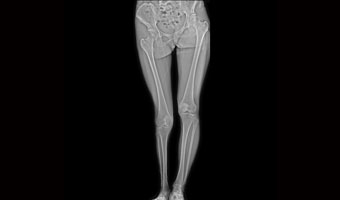

Klinik Vakalar

Tam klinik uygulama, her yerde bakım

Ortopedik yaralanmalar

Tek çekimde tam omurga ve alt ekstremite görüntüleme.

Uygulama Görüntüleri